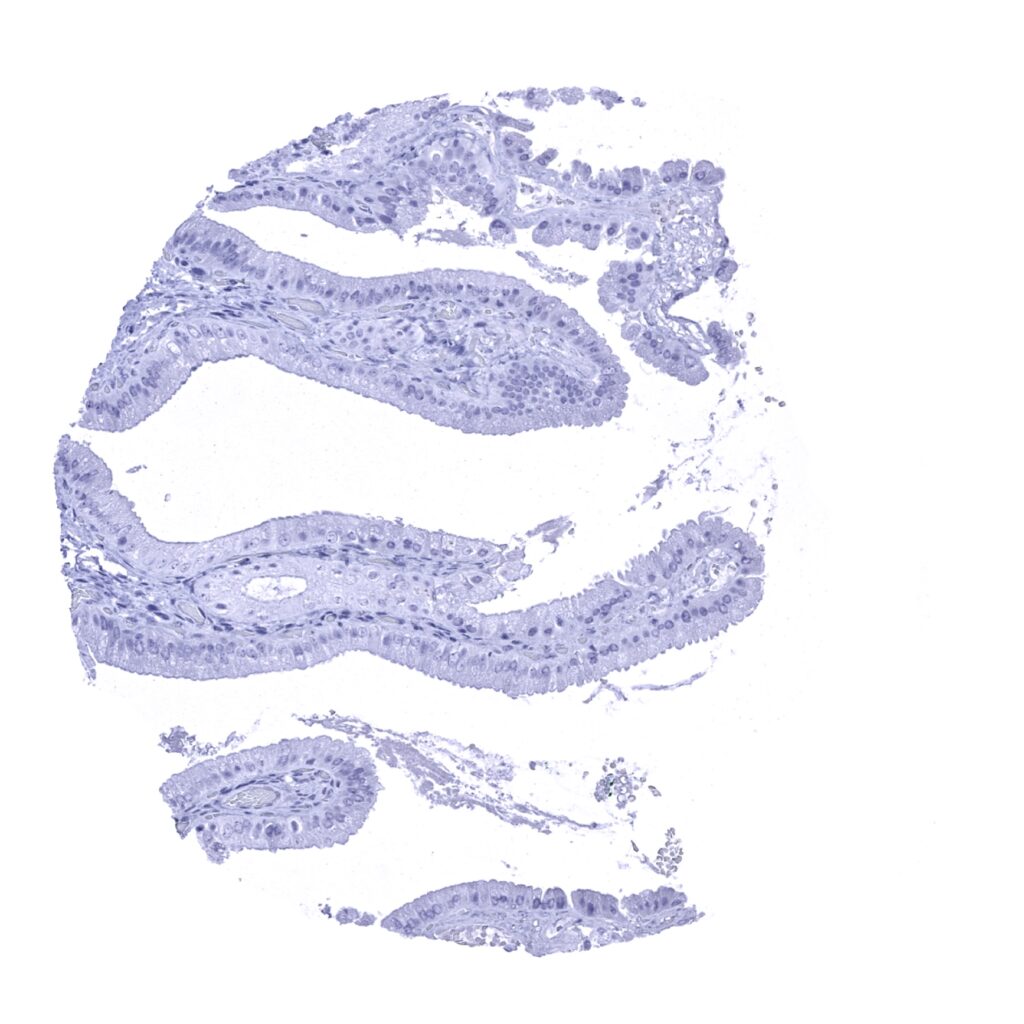

Fallopian tube, mucosa – A predominantly apical cytoplasmic Kallikrein 7 staining in a small fraction of epithelial cells.

Fallopian tube, mucosa – Kallikrein 7 staining of epithelial cells is not seen in this sample.